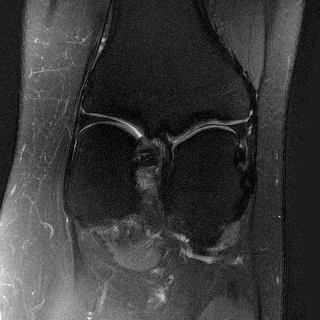

Side

Measurement

ContextMRI

RFJSearch (Ours)

Ground Truth

PDFS with PD

PD with PDFS

| PDFS with PD | ||||

|---|---|---|---|---|

| Algorithm | PSNR () | SSIM () | LPIPS () | NMI () |

| RFJS | 25.85 | 0.801 | 0.375 | 0.457 |

| GS | 25.33 | 0.797 | 0.375 | 0.455 |

| BON | 25.47 | 0.797 | 0.376 | 0.454 |

| ContextMRI | 25.39 | 0.795 | 0.383 | 0.451 |

| PD with PDFS | ||||

| RFJS | 27.85 | 0.920 | 0.358 | 0.579 |

| GS | 27.80 | 0.920 | 0.360 | 0.579 |

| BON | 27.80 | 0.918 | 0.366 | 0.570 |

| ContextMRI | 27.46 | 0.915 | 0.375 | 0.563 |

MRI with multi-contrast side information: Finally, we test on fastMRI knee dataset (Zbontar et al.,, 2018) with the ContextMRI model (Chung et al.,, 2025). We pair PD and PDFS contrasts, reconstructing one from the other under highly accelerated undersampling with 2% ACS. We use normalized mutual information (NMI) as reward, which is robust to contrast changes. Table 6 shows our methods consistently outperform the baseline in all the metrics of interest. Figure 6 highlights sharper edges and more faithful structure.